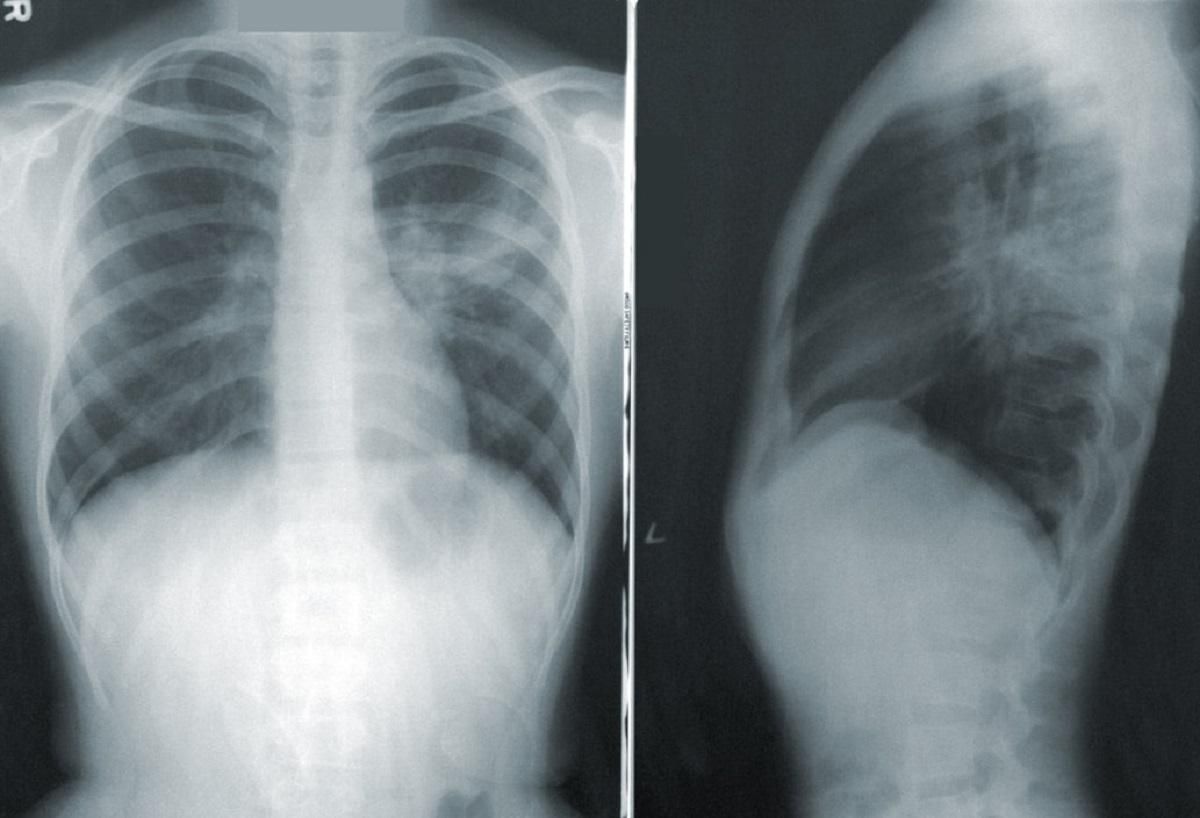

Больной 3 недели страдал от сухого кашля, лихорадки и одышки. Во время госпитализации на его рентгеновских снимках медики обнаружили коллапс легкого.

У пациента диагностировали напряженный пневмоторакс, который возникает тогда, когда воздух задерживается в плевральной полости под давлением. Такое состояние может возникать от тяжелой травмы грудной клетки, перелома ребра, вследствие дайвинга или прогулок на большой высоте.

Учитывая историю болезни, обследования и рентгенологические результаты, вполне вероятно, что этот пациент страдал на COVID-19, который потом осложнился пневмотораксом,

– рассказали в больнице.

Мужчине оказали экстренную помощь с введением дыхательной трубки и провели дренаж легкого.